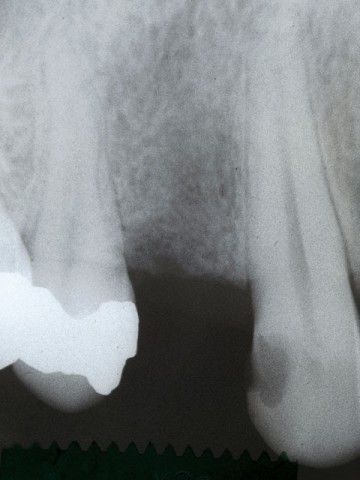

“Στις παρακάτω φωτογραφίες προβάλλονται δύο παλιά περιστατικά. Το πρώτο είναι το πρώτο μας εμφύτευμα και είναι το μακροβιότερο από όσα έχουν τοποθετηθεί στην Κρήτη! Το δεύτερο είναι μια μεγαλύτερη αποκατάσταση από το 1997”

ΠΡΩΤΟ ΠΕΡΙΣΤΑΤΙΚΟ